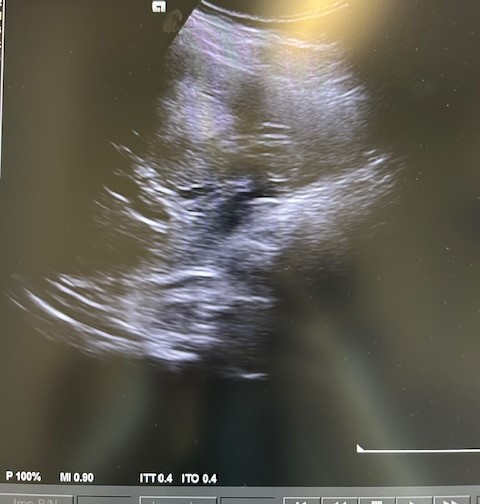

En la ecografía podemos apreciar hepatomegalia > 16 cm con múltiples imágenes en su interior hiperecogénicas sugestivas de LOE. No otros hallazgos a destacar.

El paciente fue valorado en Consultas Externas confirmando el diagnóstico. Se realiza ecografía abdominal con hallazgos de múltiples nódulos hepáticos de entre 12-35mm. En la colonoscopia, neoplasia circunferencial con aumento de consistencia, áreas ulceradas y necrosis, con estenosis incompleta, siendo compatible con adenocarcinoma de sigma.